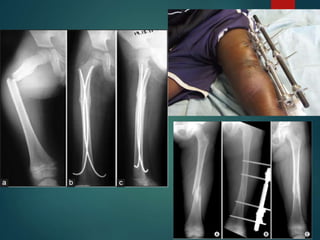

Tibial Shaft Fractures

 Mechanism of Injury

 Can occur in lower energy, torsion type injury (e.g., skiing)

 More common with higher energy direct force (e.g., car bumper)

 Open fractures of the tibia are more common than in any other long

bone

 Open Tibia Fx

 Priorities

– ABC’S

– Associated Injuries

– Tetanus

– Antibiotics

– Fixation

 Gustilo and Anderson Classification of Open Fx

 Grade 1

 <1cm, minimal muscle contusion, usually inside out mechanism

 Grade 2

 1-10cm, extensive soft tissue damage

 Grade 3

 3a: >10cm, adequate bone coverage

 3b: >10cm, periosteal stripping requiring flap advancement or free flap

 3c: vascular injury requiring repair

 Tscherne Classification of Soft Tissue Injury

 Grade 0- negligible soft tissue injury

 Grade 1- superficial abrasion or contusion

 Grade 2- deep contusion from direct trauma

 Grade 3- Extensive contusion and crush injury with

possible severe muscle injury

 Management of Open Fx

Soft Tissues

 ER: initial evaluation 

wound covered with sterile

dressing and leg splinted,

tetanus prophylaxis and

appropriate antibiotics

 OR: Thorough I&D

undertaken within 6 hours

with serial debridements

as warranted followed by

definitive soft tissue cover

 Treatment Options

 IM Nail

 ORIF with Plates

 External Fixation

 Cast or Cast-Brace